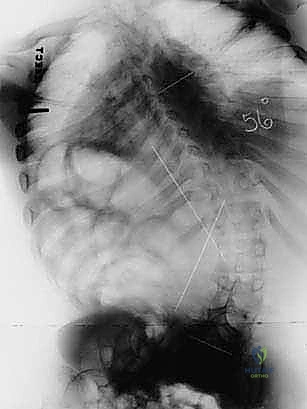

FIG 4 • Neuromuscular spinal deformity: spastic lordoscoliosis with S-hooks. These images demonstrate the long-term stability and correction achieved with S-rod fixation.